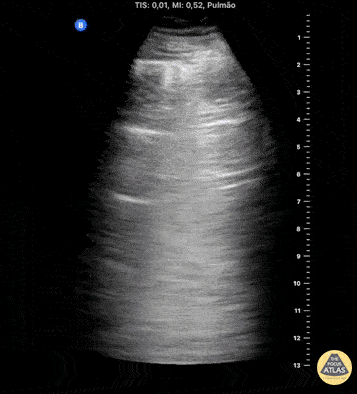

Lung ultrasound in the right apical region after puncture attempt for central venous access. The image demonstrates a LUNG POINT, a specific sign of a pneumothorax. Contributed by: Breno Moura